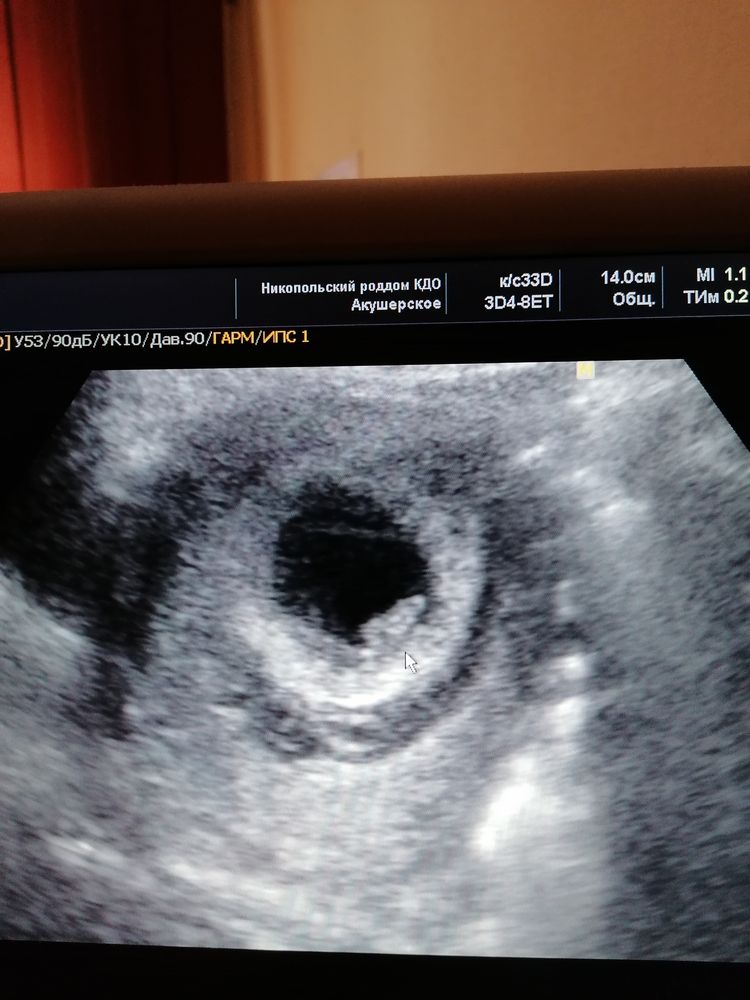

вот моё первое, 5 недель эмбриональных и 6 поставили по узи, плодное яйцо 21 мм, ктр 6.9 мм и собственно плод уже видно